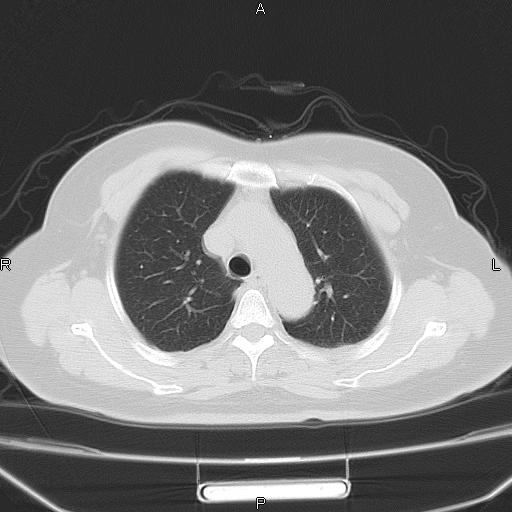

胸腺瘤

女、63Y 双眼睑下垂,早轻晚重。 胸腺瘤???

结果胸腺瘤